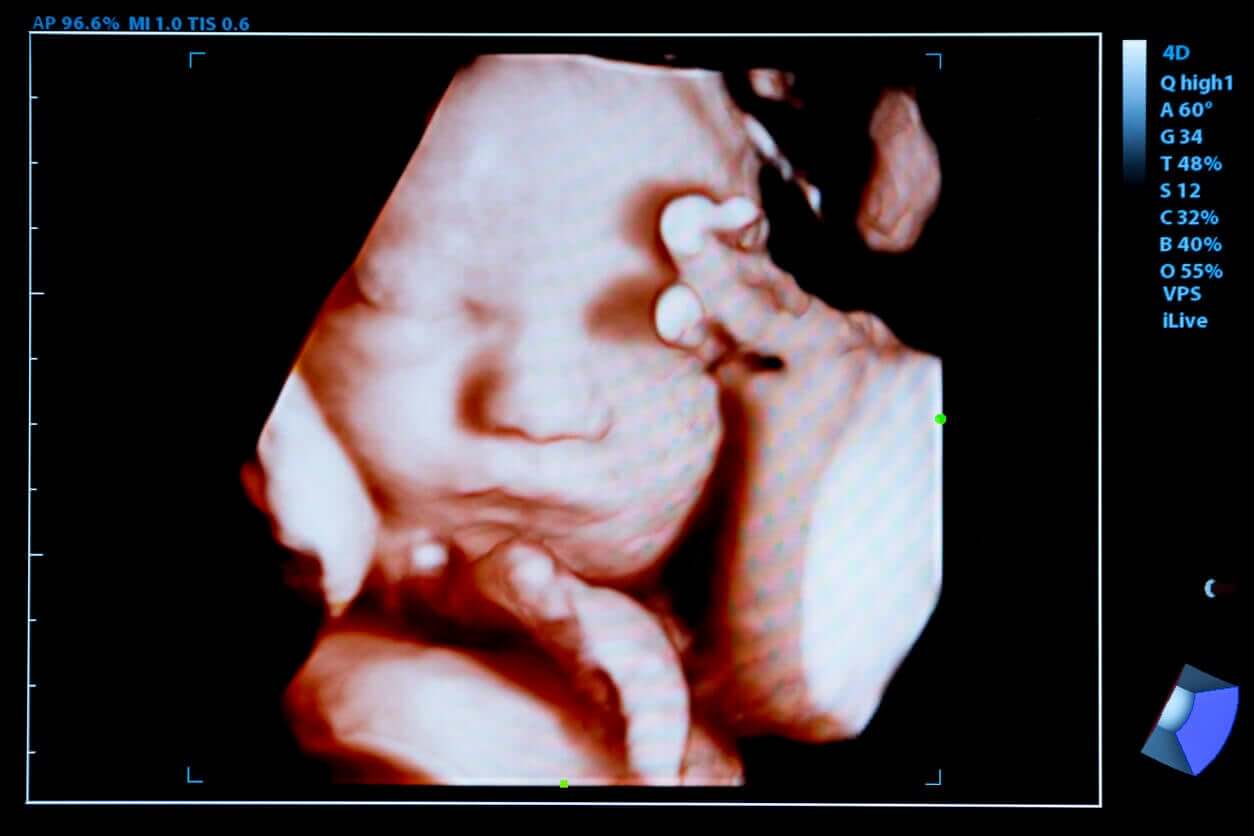

4D ultrasound is a technique by which consecutive images of the baby are obtained within the mother’s womb in a clearer way. To such an extent, that they allow you to observe the little one in motion like a video in real-time.

4D ultrasound is a novel diagnostic test that allows detailed images of the fetus to be obtained through high-frequency ultrasound waves. Unlike the previous ones, it manages to reproduce around 24 3D images in one second and gives them movement.

Then, in addition to a detailed examination of the child’s body, you can see different movements that the child makes, such as smiling, thumb sucking, or yawning.

These moving images are projected on the screen and can also be recorded on CD to preserve the memory of that beautiful experience.